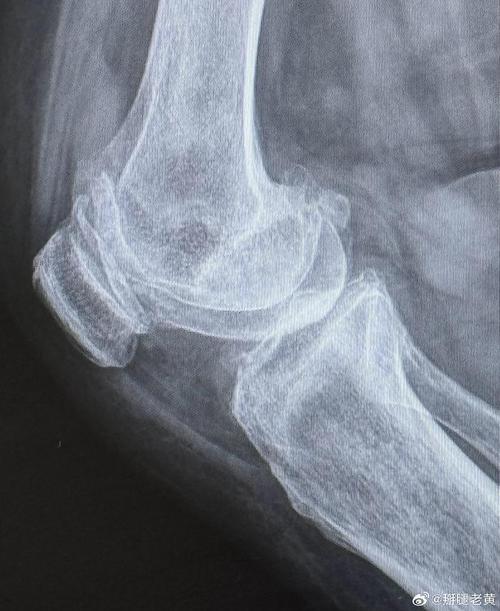

- 关节积液:表现为关节囊内脂肪垫被推挤、移位,尤其是在膝关节的髌下脂肪垫。

中晚期RA(出现特征性破坏性改变)

关节脱位/半脱位:

- 由于韧带和关节囊被炎症破坏,导致关节对位关系失常,最常见的是腕关节的月骨向掌侧脱位(舟月骨分离)和跖趾关节的半脱位。